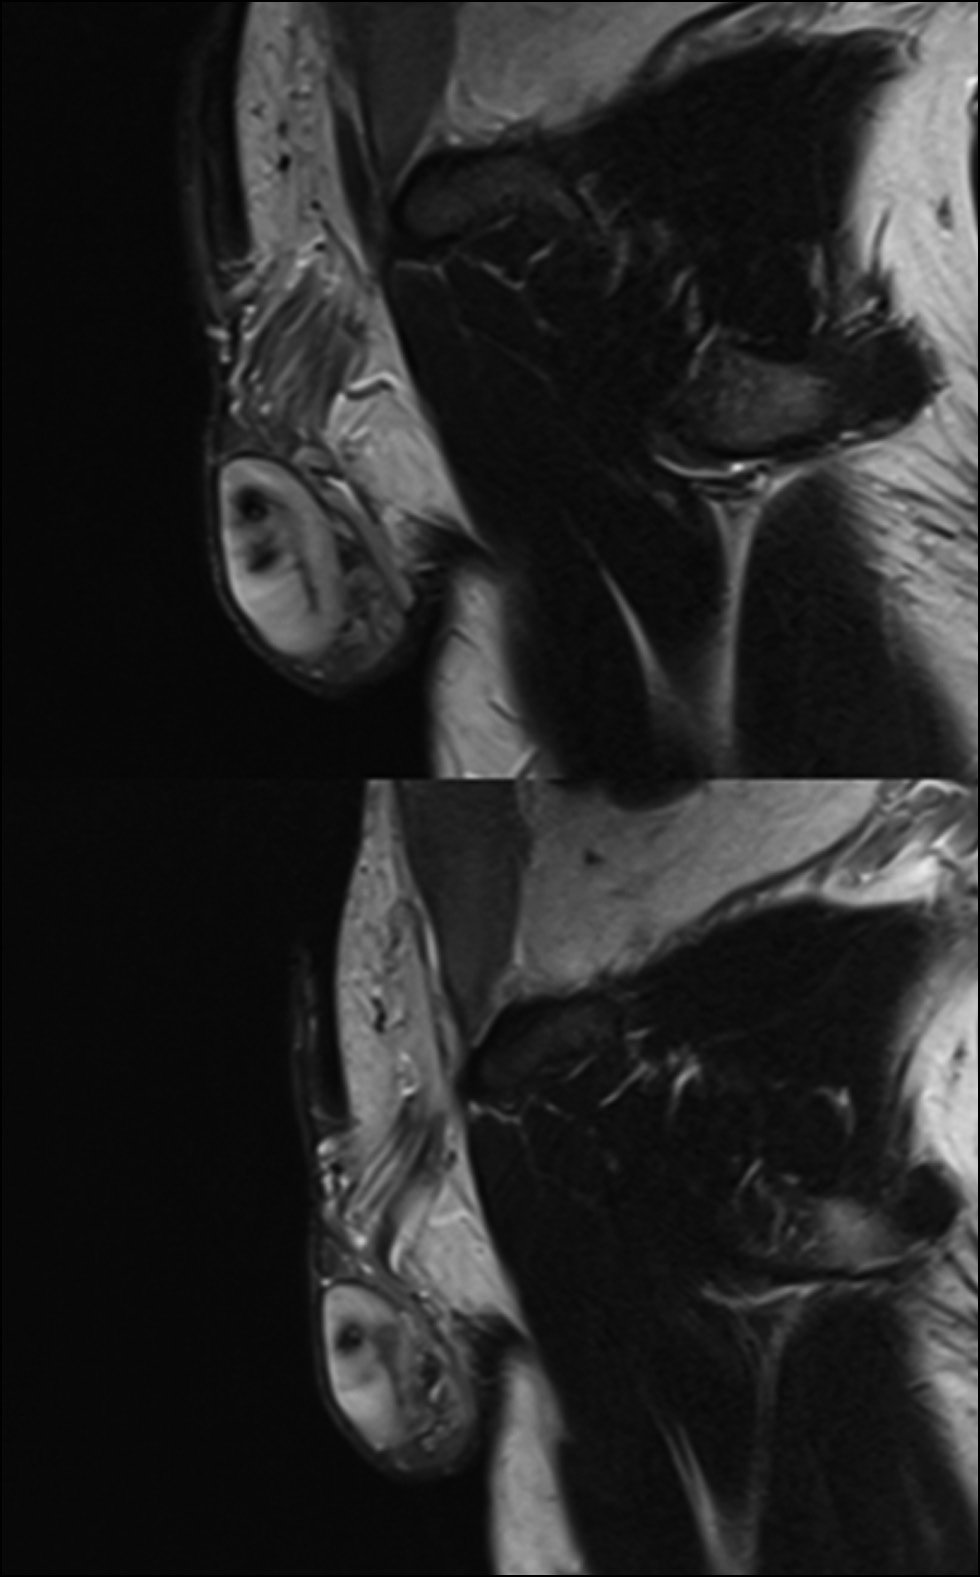

В рассматриваемом случае МРТ подтвердила нормальное расположение и морфологическую структуру правого яичка. При этом левое яичко и его придаток отличались меньшими размерами по сравнению с правым. В его структуре в области верхнего полюса был обнаружен неоднородный участок, состоящий из нескольких линейных очагов сосудистых нарушений (рис. 3–5) [6].

Рис. 3. В области верхнего полюса левого яичка (T2-взвешенное изображение) обнаружен очаг неоднородной структуры, состоящий из ряда линейных полостей, свидетельствующих о наличии ишемии.

Рис. 4. Область ишемии левого яичка на аксиальном срезе (T2-взвешенное изображение).

Рис. 5. Область гипоинтенсивного сигнала на аксиальном срезе левого яичка на разных уровнях (в режиме с последовательностью инверсии-восстановления [Short Tau Inversion Recovery, STIR]).

В данной области отмечено усиление контрастности патологического очага, характеризующееся септальным паттерном, особенно в периферической области уровня верхнего полюса. Отёчность была вызвана увеличением придатка яичка, обусловленным левосторонним варикоцеле при наличии тонкого слоя гидроцеле (рис. 6–8).

Рис. 6. Наблюдается усиление контрастности патологического очага в исследуемой области, особенно в верхнем полюсе. В Т1-режиме область даёт изоинтенсивный сигнал по сравнению с остальными тканями яичка. Выделены гиперинтенсивные участки кровоизлияний. После введения контрастного вещества (например, гадолиния) в исследуемой области выявлено отсутствие сосудов с характерным ореолом насыщенности по периферии патологического очага.